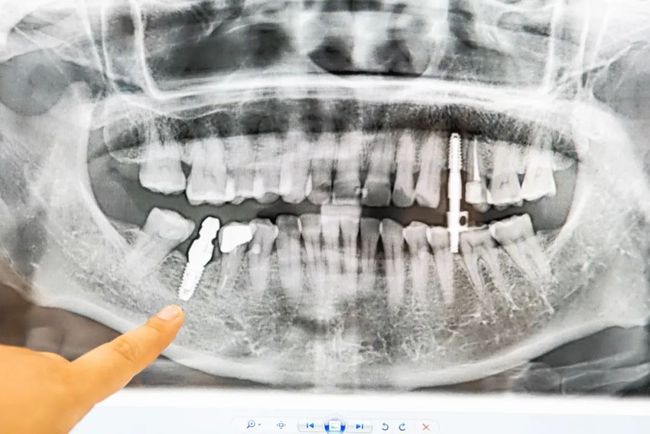

多颗缺失

种植后

前后对比图

进口优质种牙材料

而海德堡口腔选用的材料是

德国进口纯钛人工牙根

使用年限至少能达10年以上

种植牙不需要损伤两侧的邻牙,

不仅坚固耐用,还可以防止牙骨萎缩。